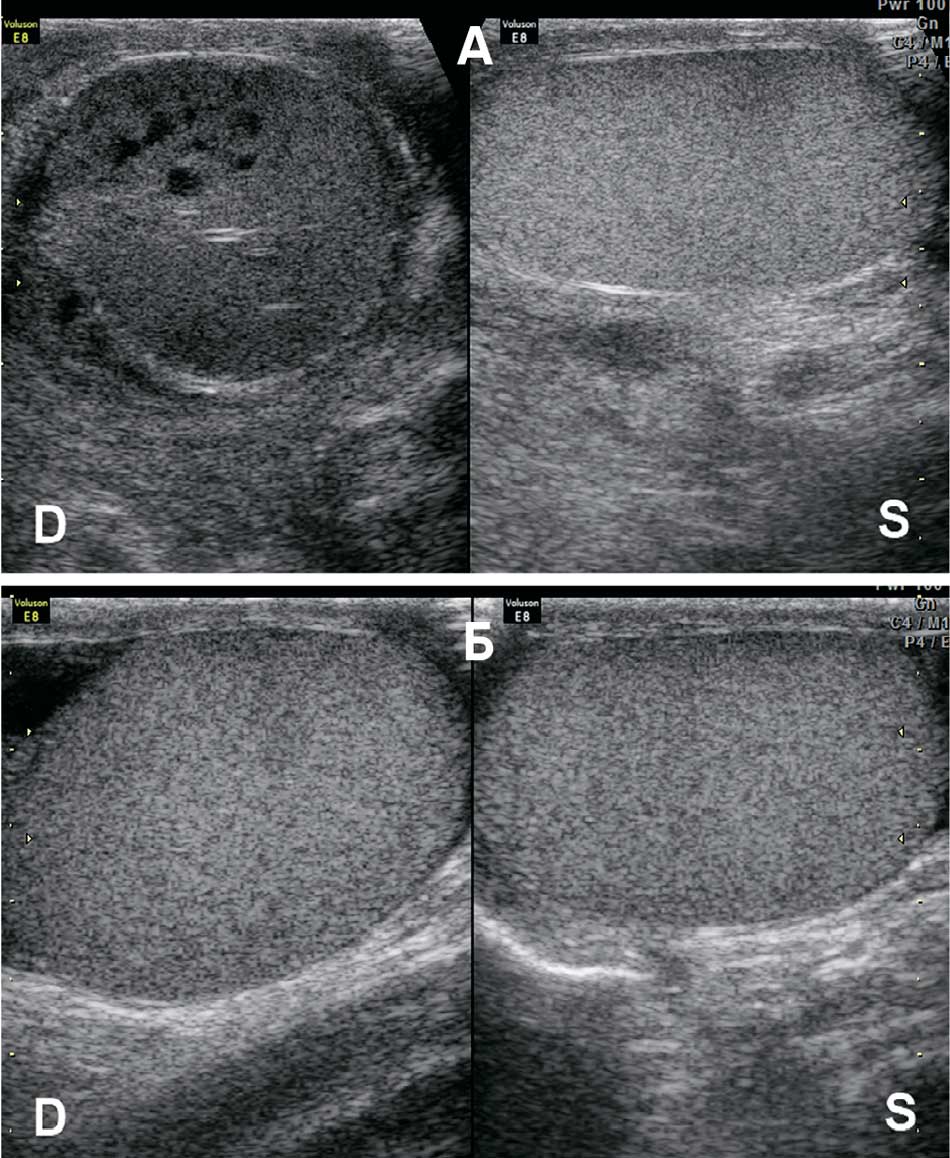

Рис. 5. Варианты эхографической визуализации перекрученных яичек:

D – правое яичко; S – левое яичко

а – перекрут правого яичка: паренхима структурна, яичко перспективно для деторсии;

б – перекрут правого яичка: паренхима неструктурна, яичко не перспективно для деторсии

Fig. 5. Options for echographic visualization of twisted testicles:

D – right testicle; S – left testicle

a – torsion of the right testicle: parenchyma is structural, testicle is amenable to detorsion;

b – torsion of the right testicle: parenchyma is not structural, testicle is not amenable to detorsion